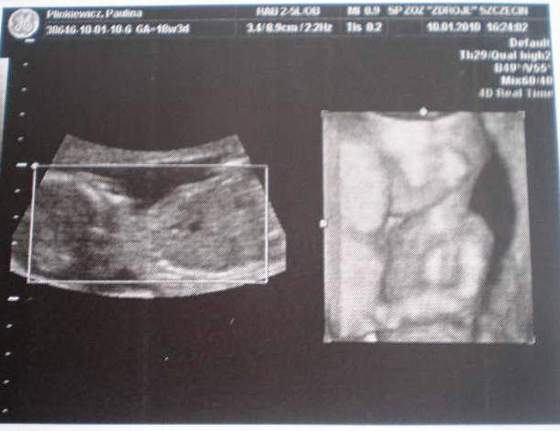

A to świeżutkie zdjęcia mojego "zagadkowego" nadal dzidziusia :-)

na tym pierwszym zdjęciu, myślałam,że to siusiak, ale to jest pępowina :-)![]()